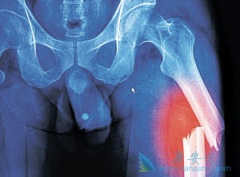

• 如何识破那些引起骨髓瘤症状的错误诊治

如何识破那些引起骨髓瘤症状的错误诊治

骨髓瘤患者的临床表现往往是身体多器官,多部位的,同时,由于人们对这个病认识不充足,导致对某些常见 骨髓瘤症状 表现,比如腰酸背痛,关节疼痛,感染现象等,常常出现误诊误治的现象,最终可能会延误治疗时机,影响预后。   如何识破那些引起骨髓瘤 ...

骨髓瘤能活多久 ?有个案例是70岁的李老太由于反复出现骨折只能入院治疗。谁知在治疗时,又被查出患有多发性骨髓瘤,这结果让李老太和她的家人都感到震惊。其实这样的事情很常见。中老年人常出现的问题骨头痛、骨折、多尿……不一定就是缺钙或者是身体 ...